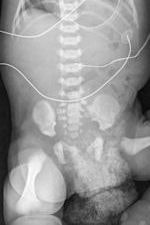

| Radiograph of newborn infant with congenital diaphragmatic hernia. Note mottled density overlying the lower pelvis caused by the wet disposable diaper. Image courtesy of Dr. Richard Markowitz. |

Dr. Richard Markowitz, a pediatric radiologist and president of the hospital's medical staff, and colleagues noticed that fluid absorbed by a wet disposable diaper appears as a myriad of small, coalescent nodular densities that have CT attenuation and MR signal characteristics. Standard radiographs also are affected.

The artifacts can obscure relevant radiographic findings, including calcifications, hernias, or pneumatosis intestinalis. They also may be misinterpreted as excreted contrast material, feces, or some other type of radiopaque material.